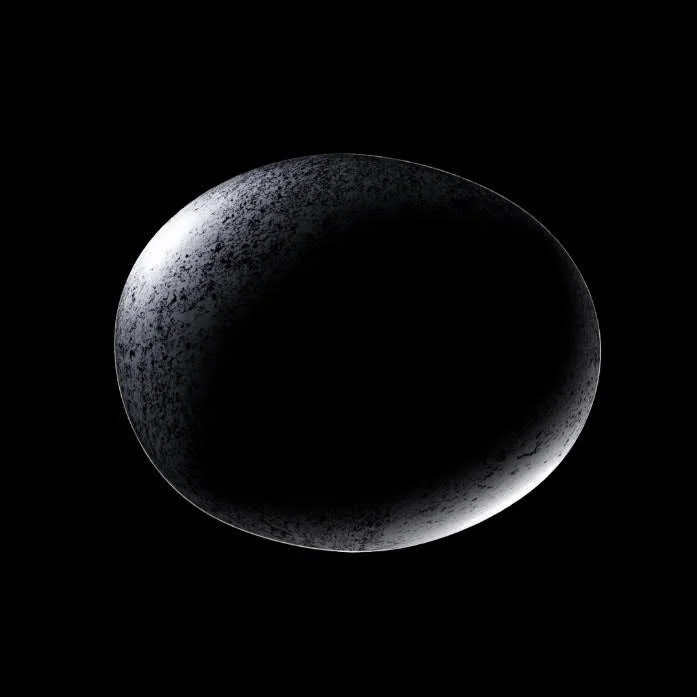

A visualization of a human embryo at the 2-week stage of development. The illustration is designed to mimic macrophotography, capturing the intricate details of this early stage with a focus on accuracy and realism.

A visualization of a human embryo at the 2-week stage of development. The illustration is designed to mimic macrophotography, capturing the intricate details of this early stage with a focus on accuracy and realism.